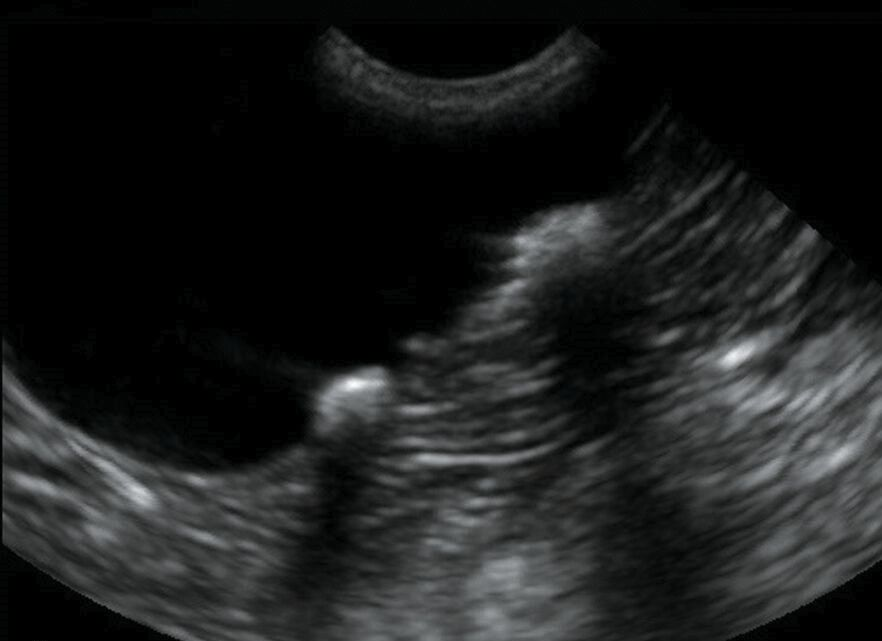

Es necesario estar en ayunas las 6-8 horas previas a la prueba. Con la ecografía renal pueden detectarse quistes tumores benignos y malignos cálculos renales piedras o en las vías urinarias malformaciones obstrucciones procesos inflamatorios o infecciosos entre otros diagnósticos. Aplica a todos los servicios de imágenes diagnósticas y servicios médicos a nivel nacional en los que se realice ecografía renal y de vías urinarias. Si se ha olvidado o no ha aguantado debe tomar abundante agua al menos desde una hora antes de la prueba y no orinar. Como además el gas colónico produce som-bra acústica en ocasiones puede parecer que se tra-ta de un cálculoP.

No se recomienda emplear cremas ni pomadas en la zona antes de la prueba ya que la prueba de imagen puede verse distorsionada. No orine antes de hacer la ecografía. Siga leyendo para más información. Otros como Daurat et al simplifican la técnica y afirman que si al realizar el cálculo de un solo eje mayor de la vejiga el diámetro es igual o mayor de 107 cm revela la presencia de retención de orina y por tanto habría que colocar un catéter. Pero también puede ser debido a la sobredistensión de la.

La ecografía prostática por vía abdominalLa prueba dura entre 5 y 10 minutos según el caso. Una ecografía sonograma es una prueba de diagnóstico por imagen que utiliza ondas sonoras para crear imágenes de estructuras del interior del cuerpo. Se suele hacer durante el embarazo para comprobar la salud del feto. Si se ha olvidado o no ha aguantado debe tomar abundante agua al menos desde una hora antes de la prueba y no orinar. Si este RPM es de más de 50-100 cc es anormal e indica un mal vaciado de la vejiga por obstrucción prostática o uretral o por debilidad en la contracción vesical.